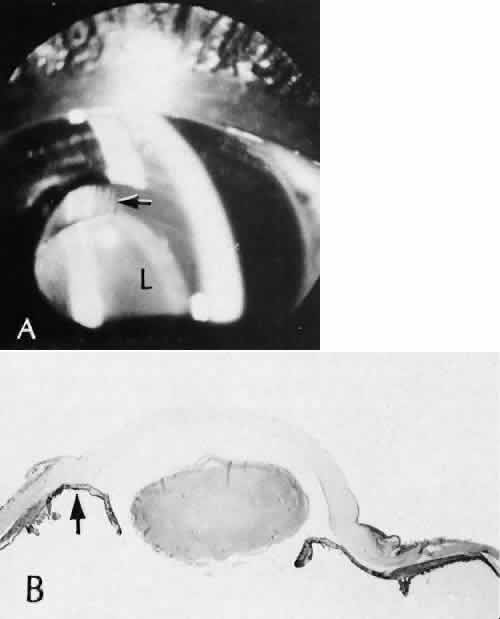

Fig. 31. A case of choroidal detachment. A. By fundus reflex, a large dome-shaped mass can be seen originating from the choroid. The differential diagnosis would include uveal malignant melanoma. In this case, the clinical findings were due to choroidal detachment from the sclera because of fluid accumulating in the suprachoroidal space following cataract surgery. B. The histologic section from another case of choroidal detachment illustrates the location (arrow) and extent of the detachment. In this case the detachment extends to the region of the ciliary body limited anteriorly by the attachment of the choroid to the scleral spur. The displacement of the ciliary body will result in apparent shallowing of the anterior chamber. (Hematoxylin-eosin stain; × 6.)

Iris or lens capsular incarceration into the wound and extending to the conjunctival space (Figs. 32 and 33) may act as a wick through which aqueous can escape, causing a flat anterior chamber. Histologically, iris, which is frequently recognized only by the presence of melanocytes, is seen in the limbal scar, in the limbal episclera, or in both areas.